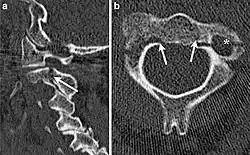

Hangman's fracture

Hangman's fracture is the colloquial name given to a fracture of both pedicles, or partes interarticulares, of the axis vertebra (C2).[1]